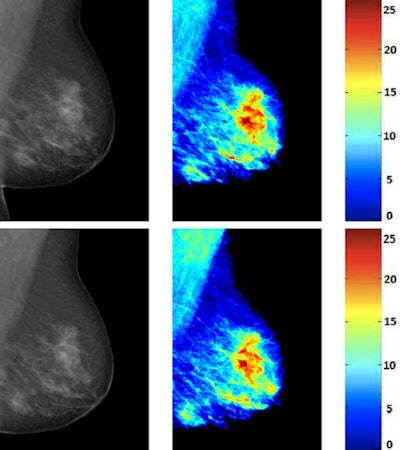

In their study, which Volpara did not fund, they sought to evaluate the repeatability of the glandular tissue measures provided by the firm's Density Maps. The software uses a physics-based model to extract pixel-wise information from raw mammograms. Few attempts have been performed for evaluating the density maps obtained using this software, according to the researchers.

García and colleagues used repeated mammograms for quantitatively assessing the variation of the density maps. There was no change in the glandularity of the breast, although several factors, such as different breast compression or different acquisition parameters, can modify the appearance and density measures of the breast, they wrote.

In their retrospective analysis of 99 repeated mammograms acquired between 2008 and 2016, the researchers compared the density and glandular tissue between the two acquisitions. They evaluated the local glandular information using histogram similarity metrics, such as intersection and correlation, and local measures, such as statistics.

They found a high correlation (breast volume R = 0.99, volume of glandular tissue R = 0.94, and volumetric breast density R = 0.96) regardless of the anode/filter material. Also, the histogram intersection and correlation metric showed for each pair the images share a high degree of information.

"Despite the different parameters of both acquisitions, the results show an important agreement," the authors wrote. "We also compare in a global way the information contained in the density maps using histogram similarity metrics, in particular the histogram intersection and correlation. Both metrics showed a high degree of similarity between the information contained in the two density maps."